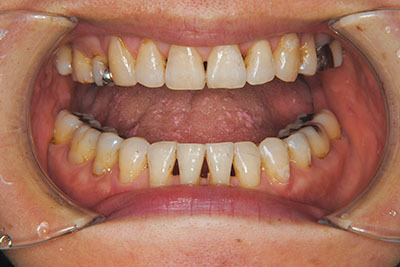

子供の頃に矯正治療を行う方が治療期間が短く済むというのは、確かですが、矯正治療は患者様の意識も重要です。

いくら歯が動き易くとも、本人がやる気でなければ効果は出ませんし、むし歯発生のリスクも高まります。おとなの方は顎の成長が終わっているため、治療の計画が立てやすいとも言えます。「もう大人だから…」とあきらめず、一度ご相談ください。